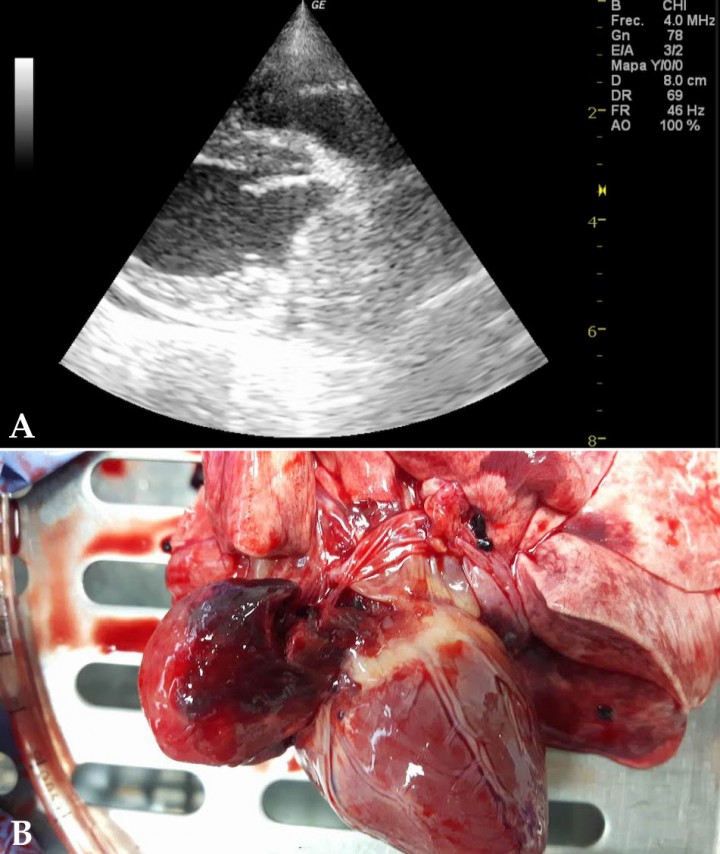

El hemangiosarcoma es el tumor más frecuente hallado en la especie canina (69 %)[ Ware WA, Hopper DL: Cardiac tumors in dogs: 1982-1995. J Vet Intern 1999; 13: 95-103. [PubMed] , Walter JH, Rudolph R: Systemic, Metastatic, eu- and heterotope tumours of the heart in necropsied dogs. Zentralbl Veterinarmed A 1996; 43: 31-45. [PubMed] ] siendo su localización más habitual la orejuela del atrio derecho (Fig. 1A). Además, pueden encontrarse en la pared del atrio izquierdo cerca o por encima del surco auriculoventricular o surco coronario. Puede presentarse de manera solitaria o junto con una masa esplénica; el grado de correlación entre las dos masas varía entre un 8,7 % y un 25 %.[ Boston SE, Higginson G, Monteith G: Concurrent splenic and right atrial mass at presentation in dogs with HSA: a retrospective study. J Am Anim Hosp Assoc 2011; 47: 336-341. [PubMed] , Waters DJ, Caywood DD, Hayden DW, Klausner JS: Metastatic pattern in dogs with splenic hemangiosarcoma– clinical implications. J Small Anim Pract 1988; 29: 805 814. ]

<p>Imágenes macroscópicas de tumores cardiacos <em>post mortem</em>. (<strong>A</strong>) Hemangiosarcoma. (<strong>B</strong>) Quemodectoma. (<strong>C</strong>) Mesotelioma.</p>

Imágenes macroscópicas de tumores cardiacos post mortem. (A) Hemangiosarcoma. (B) Quemodectoma. (C) Mesotelioma.

Tumores de cuerpo aórtico

El más frecuente de este tipo de tumores, llamados así por su localización, es el quemodectoma (Fig. 1B). Se originan a partir de las células quimiorreceptoras de la base del corazón y son tumores no funcionales con un bajo potencial metastásico.

Mesotelioma

No es de los tumores más frecuentes pero suponen el 5 % de las neoplasias que causan derrame pericárdico.[ Ware W, Hopper D: Cardiac tumors in dogs: 1982-1995. J Vet Intern Med 1999; 12:95-103. [PubMed] , Berg R, Wingfield W: Pericardial effusion in the dog: a review of 42 cases. J Am Anim Hosp Assoc 1984; 20:721-730. [PMC] ] Los signos clínicos que presenta suelen ser consecuencia del acúmulo de un gran volumen de derrame. La implicación pericárdica puede ocurrir de forma aislada o afectando también a otras superficies mesoteliales (pleura) (Fig. 1C).

<p>(<strong>A</strong>) Ecocardiografía en corte paraesternal derecho, eje largo, cuatro cámaras. Imagen compatible con masa en atrio derecho (entre flechas). (<strong>B</strong>) Imagen macroscópica donde se aprecia la visualización de masa en aurícula izquierda <em>post mortem</em>.</p>

(A) Ecocardiografía en corte paraesternal derecho, eje largo, cuatro cámaras. Imagen compatible con masa en atrio derecho (entre flechas). (B) Imagen macroscópica donde se aprecia la visualización de masa en aurícula izquierda post mortem.